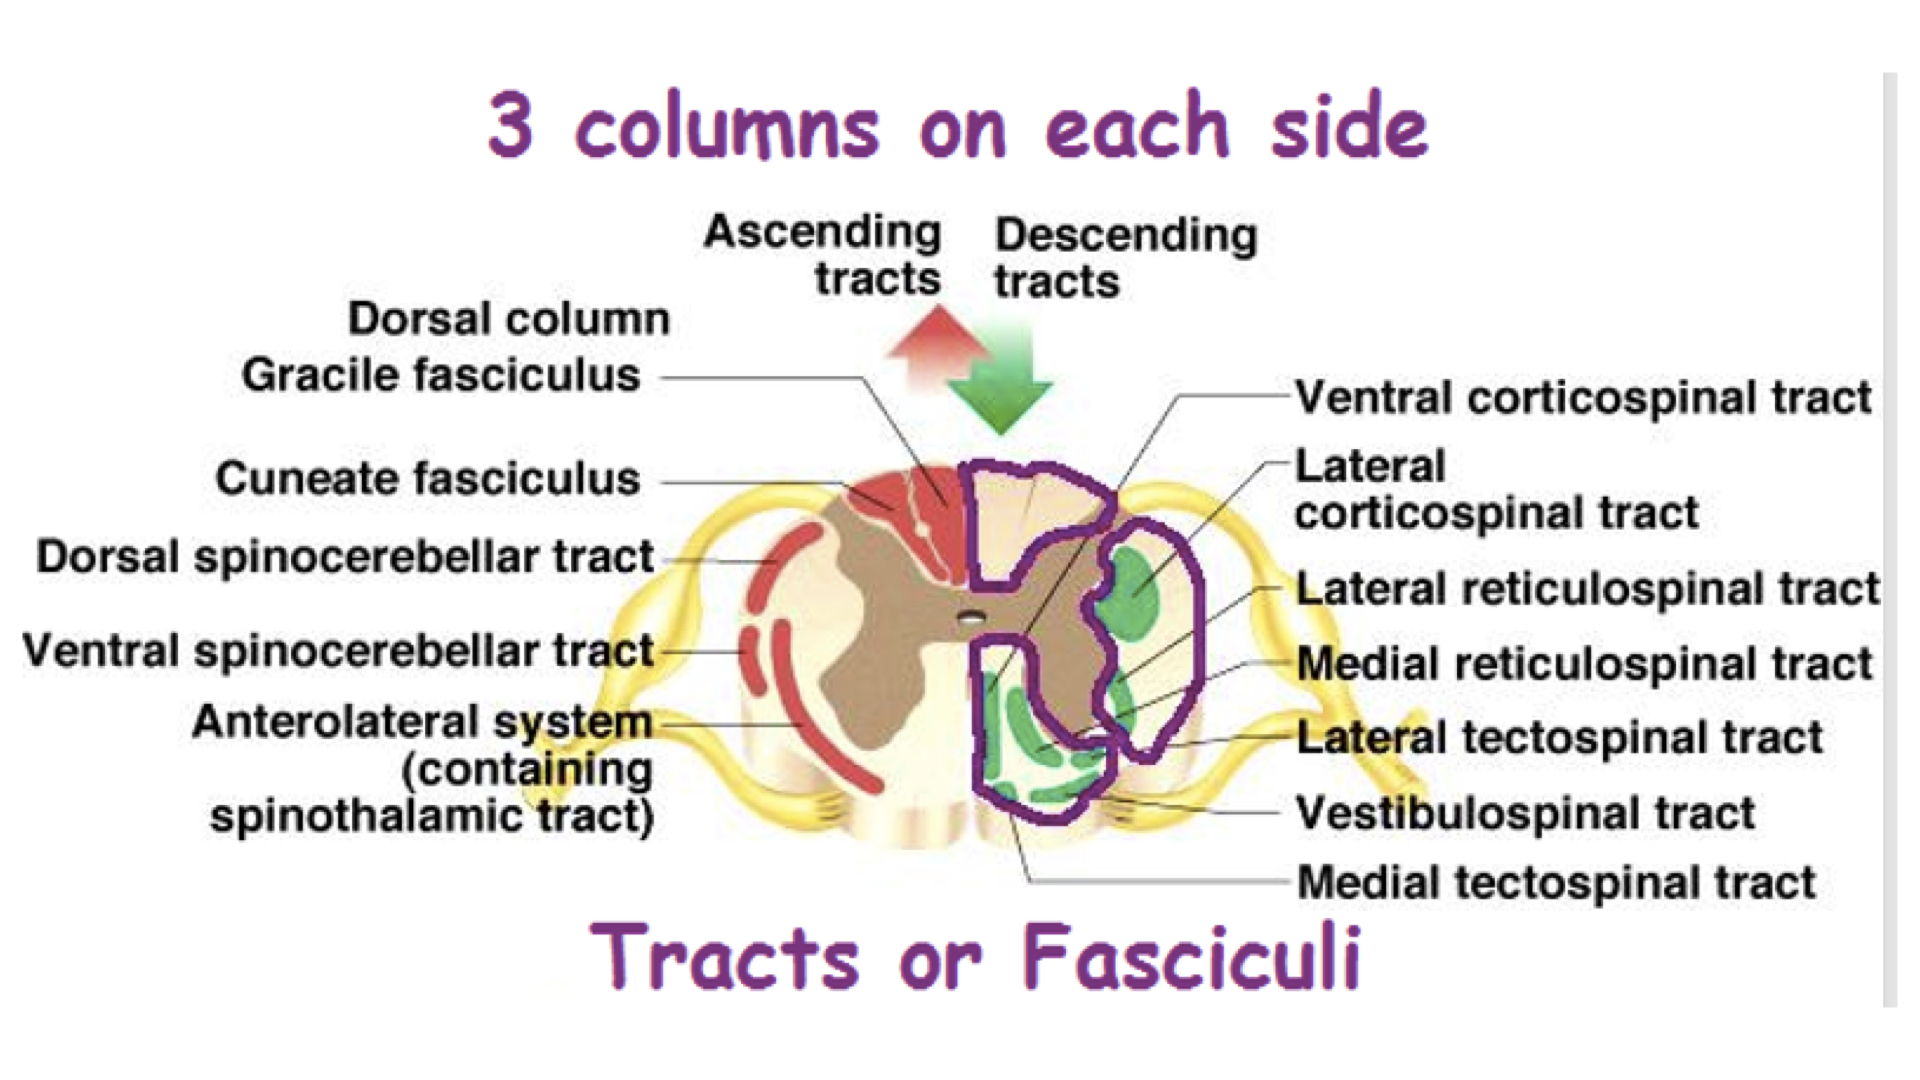

b. contains six fasciculi

1. Two posterior

2. Two lateral

3. Two anterior

c. Ascending and descending tracts are located in the fasciculi

1. share common origins, destinations, and functions

d. A column is a group of tracts